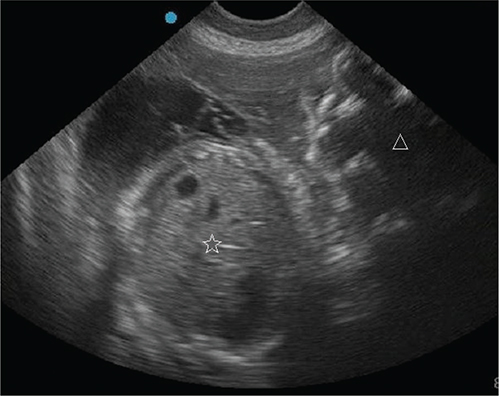

The dog was presented for an outpatient reexamination once more (on day 56 after breeding). The dog had 2 episodes of vomiting since prior visit and was trembling in the car for an hour prior to the appointment. The dog had lost 0.5 kg since prior visit, was tachycardic (160/bpm), had mild erythema of the skin and ear pinnae, and was mildly hyperthermic (39.4°C). There was continued vulvar discharge and initial mammary secretions from a few teats, consistent with colostrum. Due to the concern for systemic inflammatory response syndrome (SIRS)6 on clinical examination (elevated temperature and tachycardia), bloodwork was performed. Patient had moderate normocytic normochromic anemia of pregnancy, with a marked neutrophilia and a left shift, and mild monocytosis. A mild hypoglycemia and mild hypocalcemia were also noted (Table). Progesterone concentrations were lower (1.10 ng/ml). Targeted transabdominal ultrasonography revealed similar findings as before (multiple normal viable fetuses and 1 dead fetus [Figure 4]). Further maturation of the live fetuses was evident by slight distinction of the cortical and medullary parenchyma of fetal kidneys (Figure 5) and a more thickening of gastrointestinal tract layers in two of the fetuses7 (Figure 6). Given the patient’s deterioration and concerning laboratory findings, immediate cesarean surgery with ovariohysterectomy was again recommended; however, surgery was declined. Recommendation was made to discontinue terbutaline (Brethine®, Hikma Pharmaceuticals PLC) and altrenogest (Regu-Mate®, Merck Animal Health), to allow the dog to whelp at home. Amoxicillin and clavulanate potassium (Clavamox®, Zoetis) and ciprofloxacin (Cipro®, Bayer HealthCare Pharmaceuticals Inc.) were continued.

Fig. 4.

Figure 4. Transabdominal ultrasonographic image of live (star) and autolyzed (triangle) fetuses.